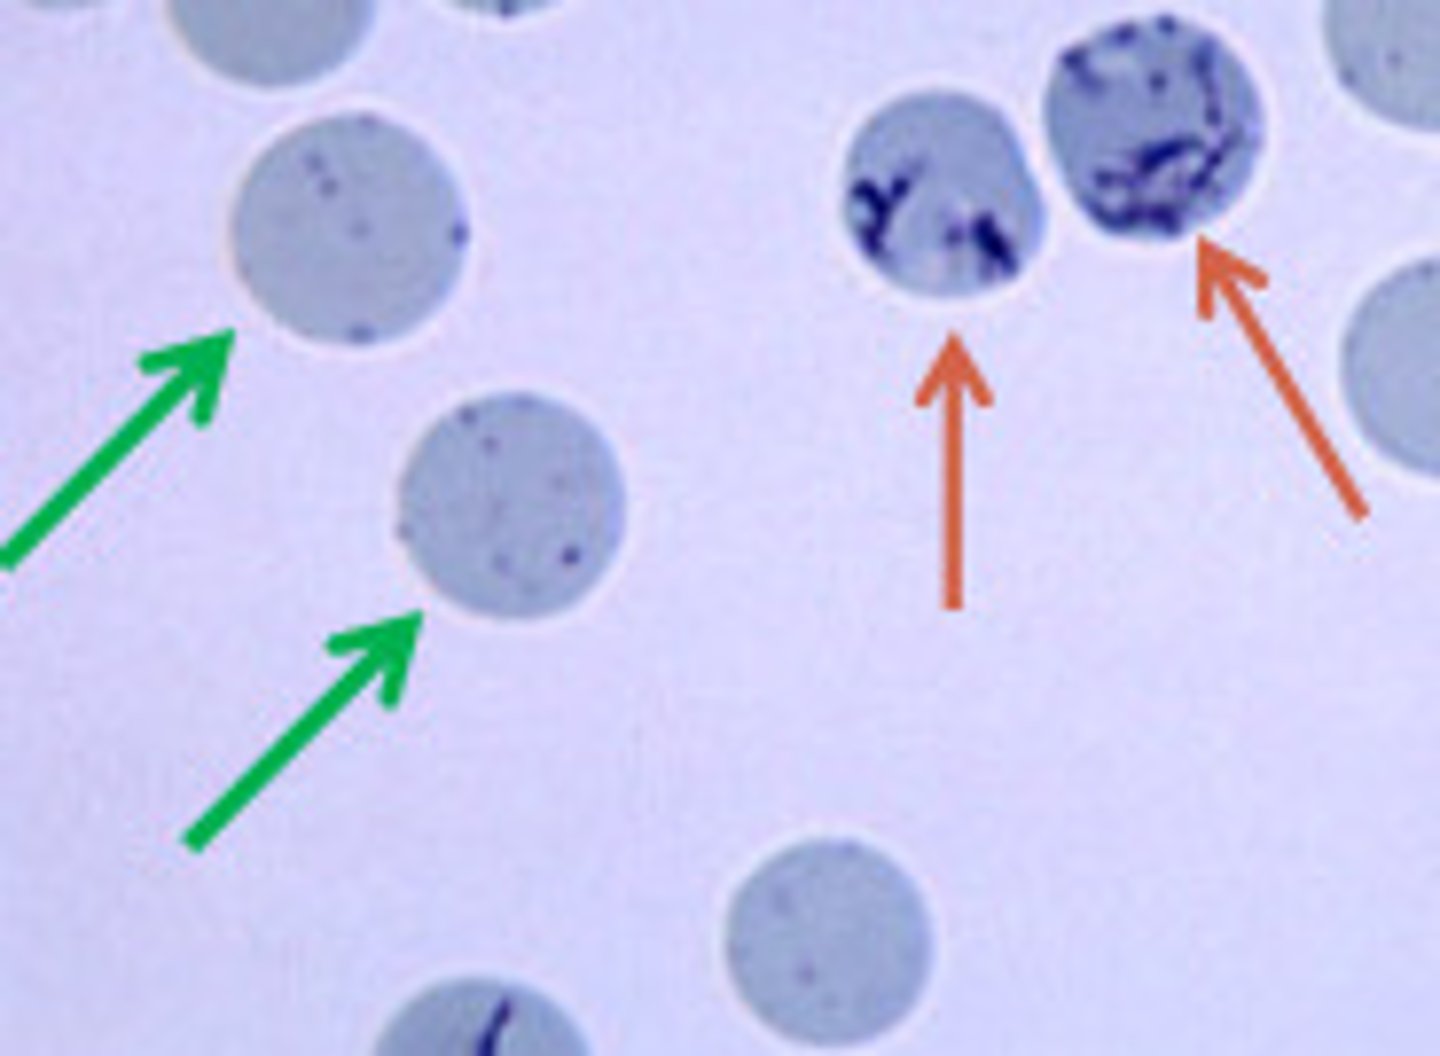

aggregate reticulocytes

orange arrow

hint: NMB stain

punctate reticulocytes

**not counted

green arrow